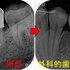

レントゲン

2026 EEdental YOA (1).jpg

外枠は外さず真ん中からくり抜くように治療したようです。